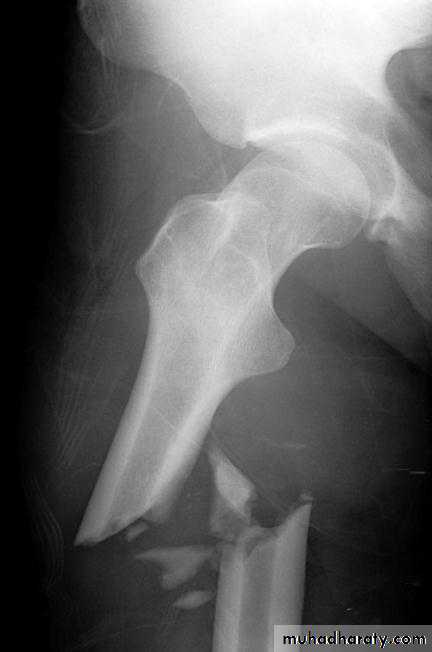

Some fractures (example fracture of femoral shaft) are difficult to reduce by manipulation because of powerful muscle pullHowever, they can be reduced by sustained mechanical traction.